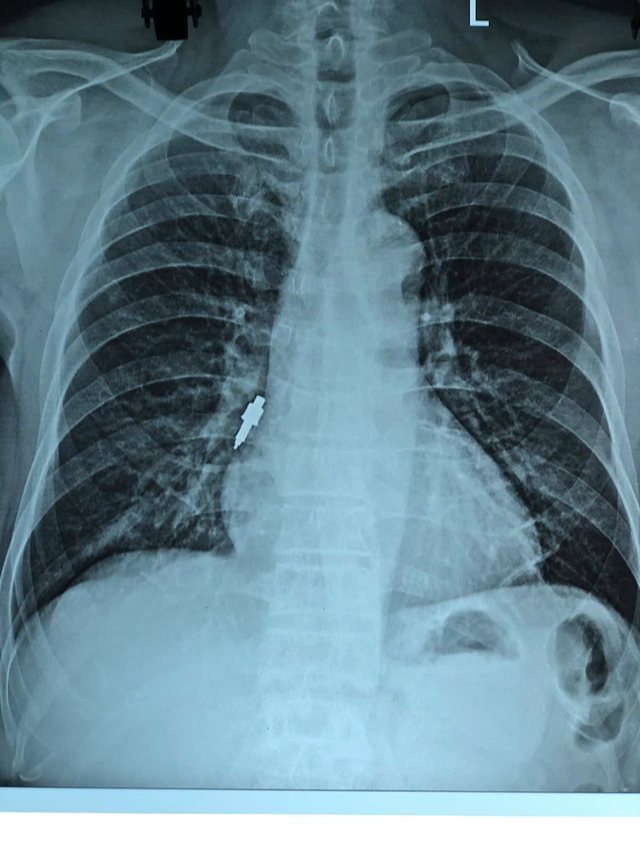

Qua khai thác bệnh nhân cho biết cách đây khoảng hai tuần có thực hiện thủ thuật đặt Implant tại một phòng khám răng tư nhân. Trong quá trình thao tác, bác sĩ nha khoa thông báo có đánh mất một dụng cụ nhưng không xác định được vị trí rơi. Sau khi về, bệnh nhân xuất hiện ho nhẹ kéo dài và tăng dần nên đến bệnh viện thăm khám. Kết quả chụp X-quang cho thấy người bệnh có dị vật nằm tại phế quản phải. Quá trình nội soi cấp cứu trường hợp trên gặp nhiều khó khăn do dị vật to, trơn, mắc sâu trong phế quản.

Nhằm đảm bảo an toàn tối đa cho người bệnh, ê-kíp thủ thuật phối hợp thao tác cẩn trọng để hạn chế nguy cơ chảy máu, rách phế quản hoặc đẩy dị vật sâu hơn. Sau khi gắp thành công dị vật, phế quản bệnh nhân được bơm rửa sạch mủ, cặn máu trong lòng đường thở, người bệnh hiện tỉnh táo, giảm ho rõ rệt.

Theo TS. BS Nguyễn Tiến Dũng (Trưởng khoa hô hấp dị ứng – Bệnh viện Hữu Nghị) do dị vật lớn, trơn và cắm chặt vào phế quản nên không thể gắp bằng kìm sinh thiết – loại thường dùng với các dị vật thông dụng như hạt lạc, xương cá… Nếu không được phát hiện sớm, dị vật kích thước lớn như vậy có thể gây nhiều biến chứng nguy hiểm: tắc nghẽn đường thở, viêm phổi, áp-xe phổi, thậm chí suy hô hấp đe dọa tính mạng.